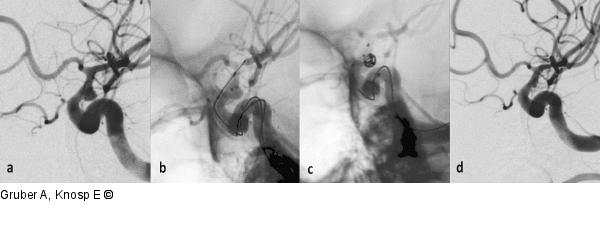

Abbildung 7a-d: Coil-Embolisation Ballongestützte Coil-Embolisation. (a) Angiographien der Arteria carotis interna im seitlichen Strahlengang zeigen ein breitbasiges Aneurysma der Karotishinterwand unmittelbar distal des Duradurchtritts. Das Aneurysma ist für eine konventionelle Coil-Embolisation zu breitbasig, die stentgestützte Coil-Embolisation ist in der Akutphase nach aSAB problematisch. Eine Alternative zur mikrochirurgischen Clippung – mit Clinoidresektion und proximaler Gefäßkontrolle durch Karotisfreilegung am Hals bzw. Ballonprotektion – besteht in der ballongestützten Coil-Embolisation. (b) Dabei werden 2 Mikrokathetersysteme gleichzeitig in das aneurysmatragende Gefäß hochgeführt, ein Mikrokatheter wird im Aneurysma, ein Ballonkatheter vor dem breiten Aneurysmahals im Gefäß positioniert. Durch intermittierendes Befüllen des Ballons während des Absetzens der Coils kann das Prolabieren der Coils in das Gefäß verhindert (c) und das Aneurysma korrekt verschlossen werden (d). Die Coils werden während des Einbringens in das Aneurysma durch den Widerstand des Ballons so verformt, dass sie auch nach dessen Entleerung nicht in das aneurysmatragende Gefäß zurückweichen können. Solche Ballonkatheter werden auch als „temporäre neck-bridging devices“ (im Gegensatz zu Stents und Flowdivertern, den so genannten „permanenten neck-bridging devices“) bezeichnet. Diese Methode erreicht bei großen breitbasigen Aneurysmen ihre Grenzen: Einerseits wird die Gesamtdauer der intermittierenden Ballonfüllung in der Akutphase nach aSAB zu lange (vgl. mit temporärer Clippung bei der Aneurysmachirurgie), andererseits ist die Langzeitstabilität des intra-aneurysmalen Coil-Paketes bei großen breitbasigen Aneurysmen suboptimal. |